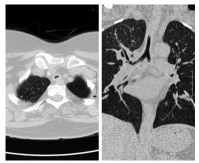

She was doing well for six months; however, she presented to emergency with history of cough, fever and wheeze for 15 days. On evaluation, she had type 2 respiratory failure and needed biphasic positive airway pressure support. Also, she was given high-dose steroids under antibiotics cover. HRCT of the chest showed worsening as expected. There was no improvement with the existing treatment even after three weeks. Patient continued having carbon dioxide retention with high respiratory rate and deterioration of sensorium despite noninvasive ventilation support. She also developed hospital-acquired infection. Discussion with the respiratory team and relatives ensued and decision for tracheal stenting was established (Figures 3 and 4).

Earlier stenting was avoided in view of long segment involvement. Post-procedure, she was put on ventilator and tracheostomized later in view of long-term ventilatory involvement. She was discharged after three weeks of hospital stay and later she suffered from post-procedure complications like tracheostomy site ulcer and its bleeding, subcutaneous emphysema and difficulty regaining activities of daily living. She was readmitted after a month with worsening of breathlessness and fever and was bound to have bilateral pneumonia. This time, she succumbed in view of sepsis and related acute kidney injury.